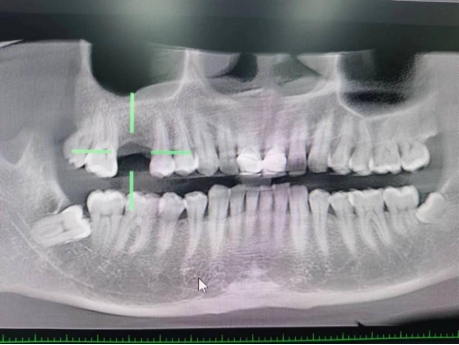

王先生术后检查图

第一台手术结束后,预约已久的王先生也在下午进行种植牙手术,据了解,在朋友的推荐下,王先生已提前完成各项检查等待手术,种植手术结束后,王先生说:“伤口没什么不适感觉,也没有感觉肿胀疼痛”。